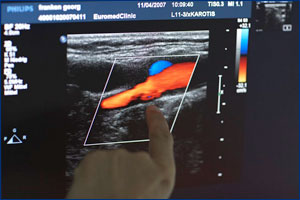

Sollten bereits Gefäßablagerungen vorliegen, können wir durch weitere Untersuchungen (Farbultraschall, Darstellung der Gefäße mit Kontrastmittel) das Ausmaß der Gefäßerkrankungen erkennen und eine Therapie einleiten, beispielsweise mit Hilfe von Kathetertechniken. Dr. med. Susanne Schell ist spezialisiert auf Ultraschalldiagnostik. Zusätzliche Bluttests (Bestimmung des Blutzuckers, Cholesterin, Harnsäure etc.) liefern Messwerte, damit wir Ihnen zu einer geeigneten medikamentösen Therapie raten können.

Im Fall von Venenerkrankungen kann der Arzt bereits durch die körperliche Untersuchung erste Hinweise für ein schwaches Bindegewebe oder Thromboseneigung bei Ihnen entdecken und durch eine gezielte Diagnostik mittels Funktionstests, Farbdoppleruntersuchung und Röntgenuntersuchung die Venenfunktion untersuchen und eine individuelle Therapie bei Ihnen einleiten.